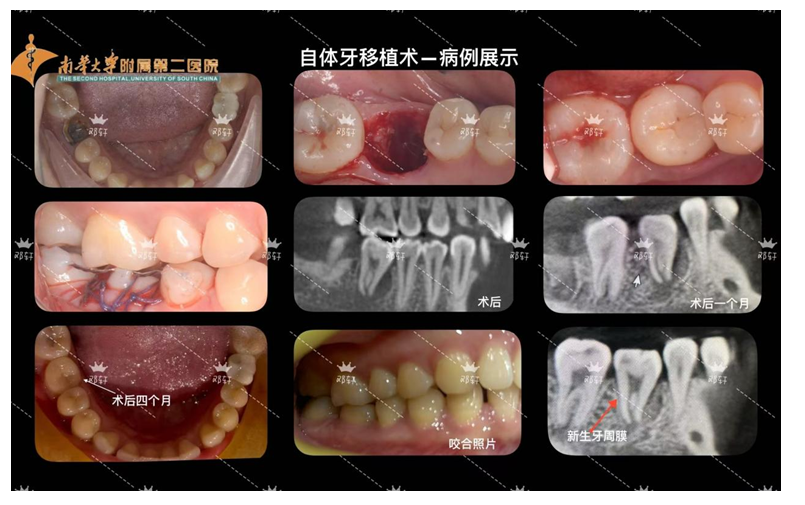

自提牙移植技术:是将患者自身的牙齿从一个位置移植到另一个需拔除患牙或缺失牙的位置上,使其在新位置愈合后行使咬合功能,恢复牙列缺损